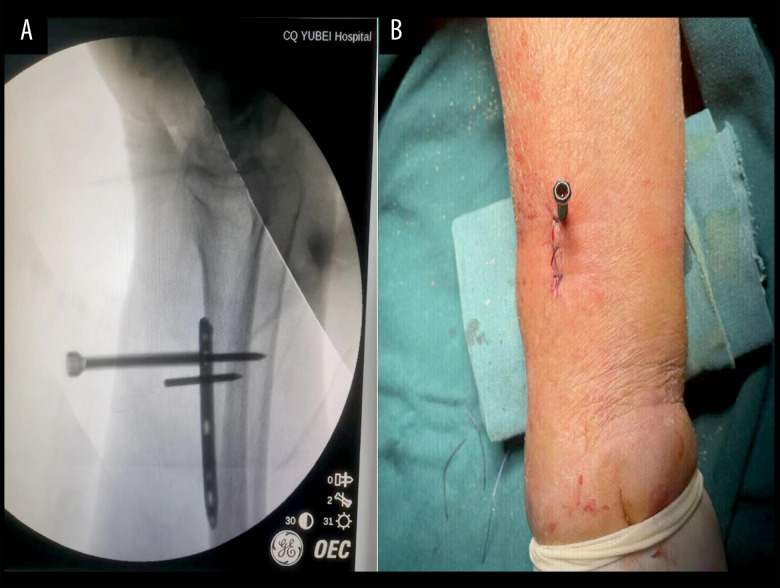

BACKGROUND Raynaud syndrome, also known as Raynaud phenomenon, is characterized by vasospasm of small blood vessels supplying the digits and is usually reversible but can rarely result in severe and irreversible ischemia. Periosteal distraction osteogenesis is a technique that creates a space between the periosteum and the bone surface to stimulate the formation of new bone. This report describes a 67-year-old woman with a 10-year history of Raynaud syndrome presenting with ischemia and gangrene of the right index and middle fingers managed with radial periosteal distraction osteogenesis. CASE REPORT Ten years earlier, the patient received a diagnosis of Raynaud syndrome and had been taking nifedipine sustained-release tablets orally for symptom control ever since. Two weeks before presentation, she successfully recovered from septic shock through the rescue of the Intensive Care Unit. One week before presentation, the patient experienced an aggravation of pain in both fingers. Her distal ends of the right index and middle fingers became darker. After performing the relevant examinations, she received a diagnosis of Raynaud syndrome (bilateral) and gangrene of the right finger. Following the exclusion of surgical contraindications, radial periosteal distraction was performed. The periosteum was continuously distracted after the operation. During follow-up, the patient's gangrene gradually progressively healed, and the pain in both hands markedly diminished. CONCLUSIONS This report supports recent studies that have shown the potential for periosteal distraction osteogenesis in the management of cases of severe and irreversible Raynaud disease of the digits.